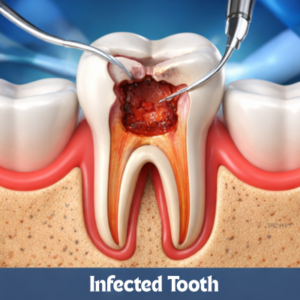

ROOT CANAL

ROOT CANAL

ROOT CANAL

ROOT CANAL